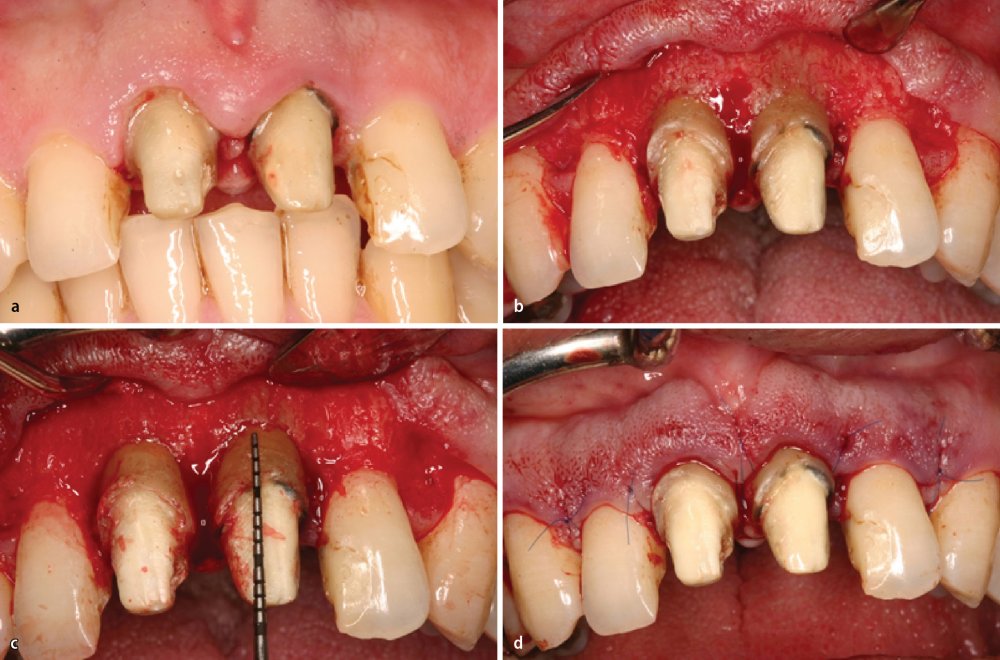

Diş tacının cərrahi uzadılması müxtəlif kliniki hallarda müxtəlif məqsədlərlə tətbiq edilən cərrahi müalicə prosedurudur. Bu metod estetik stomatologiyada “Gummy smile” (diş əti gülüşü) olaraq adlandırılan durumun ortadan qaldırılması məqsədilə geniş tətbiq olunur. Bu zaman kliniki hala bağlı olaraq bəzən yalnız diş əti, bəzən isə həm diş əti həm də sümükdən müəyyən miqdarda rezeksiya edilməklə (kəsilməklə) diş və diş ətinin estetik cəhətdən ideal görünüşü əldə olunur.